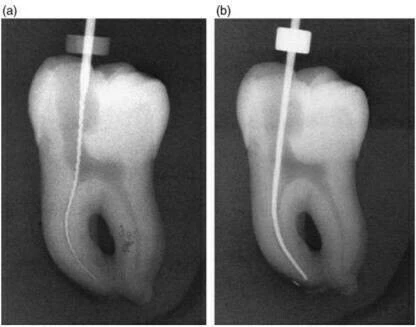

Trên phim X-quang ban đầu:

- (a) cho thấy một cây trâm số 15 góc cong 35 độ. Hình X-quang sau khi sửa soạn ống tủy

- (b) với cây trâm số 40 góc cong 13o.

Kết quả của việc sửa soạn ống tủy đã làm cho ống tủy bị chuyển dịch so với ban đầu. Có hiện tượng giảm chiều dài làm việc. Bạn có thấy rằng ống tủy đã bị làm thẳng hơn?